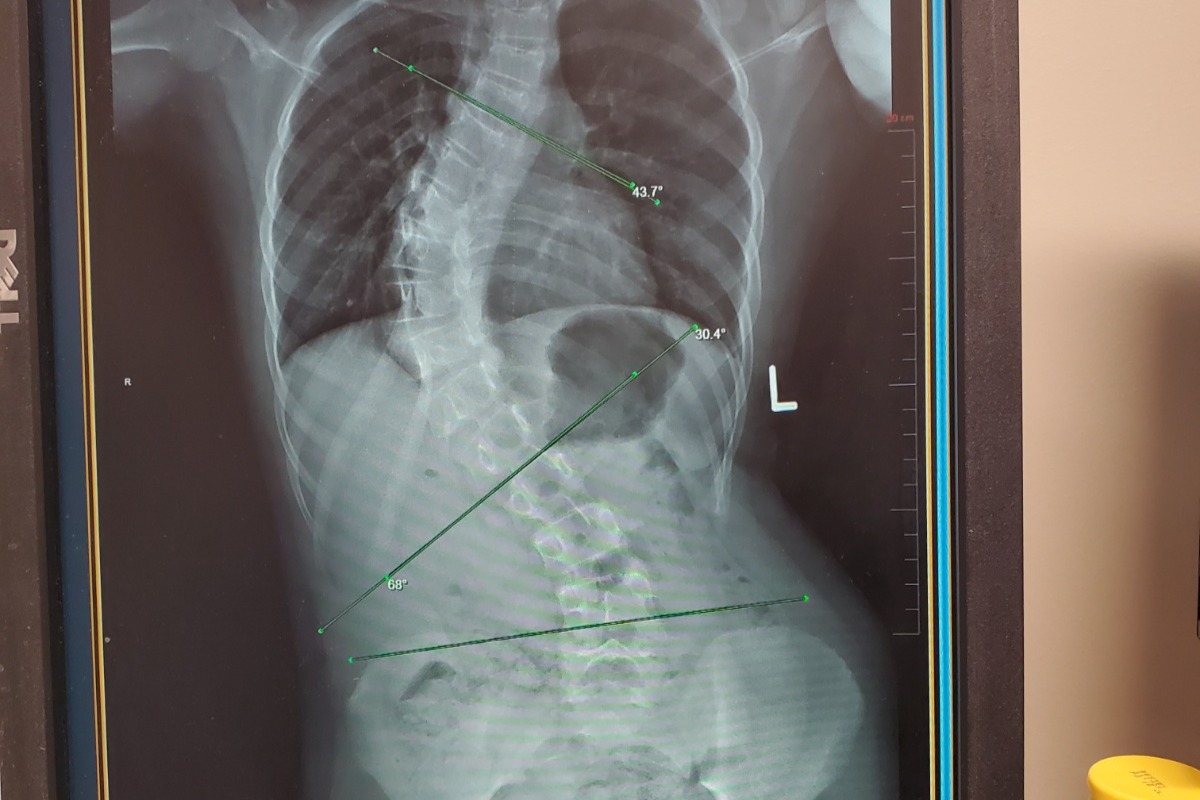

My niece, Ariana, was diagnosed with Scoliosis in 2017 when she was just 9 years old. With no success at straightening her spine despite years in a back brace, her spine is now at a 68 degree curvature. Her doctor has now recommended she undergo Spinal Fusion surgery in June of this year. She has only gone through the MRI phase and with the big surgery a couple short months away, my sister and brother in law are already being hit with bills.